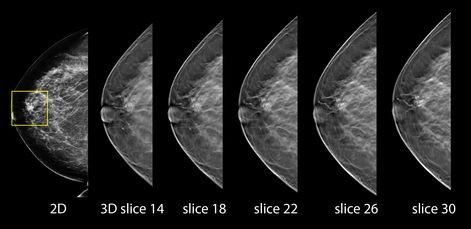

La mamografía por tomosíntesis es una técnica muy avanzada que, mediante la adquisición de 15 proyecciones de la mama con diferentes ángulos –y no una sola proyección, como hace el sistema convencional-, permite analizar el seno milímetro a milímetro. Así se consigue un diagnóstico más fiable y preciso, sin necesidad de repetir pruebas.

Crea una imagen en 3D de toda la mama, en menos tiempo de exposición

Este sistema abarca toda la mama y crea una imagen en 3D, en menor tiempo de exposición y con menos dosis de radiación, para detectar incluso los tumores más pequeños en todo tipo de mamas.